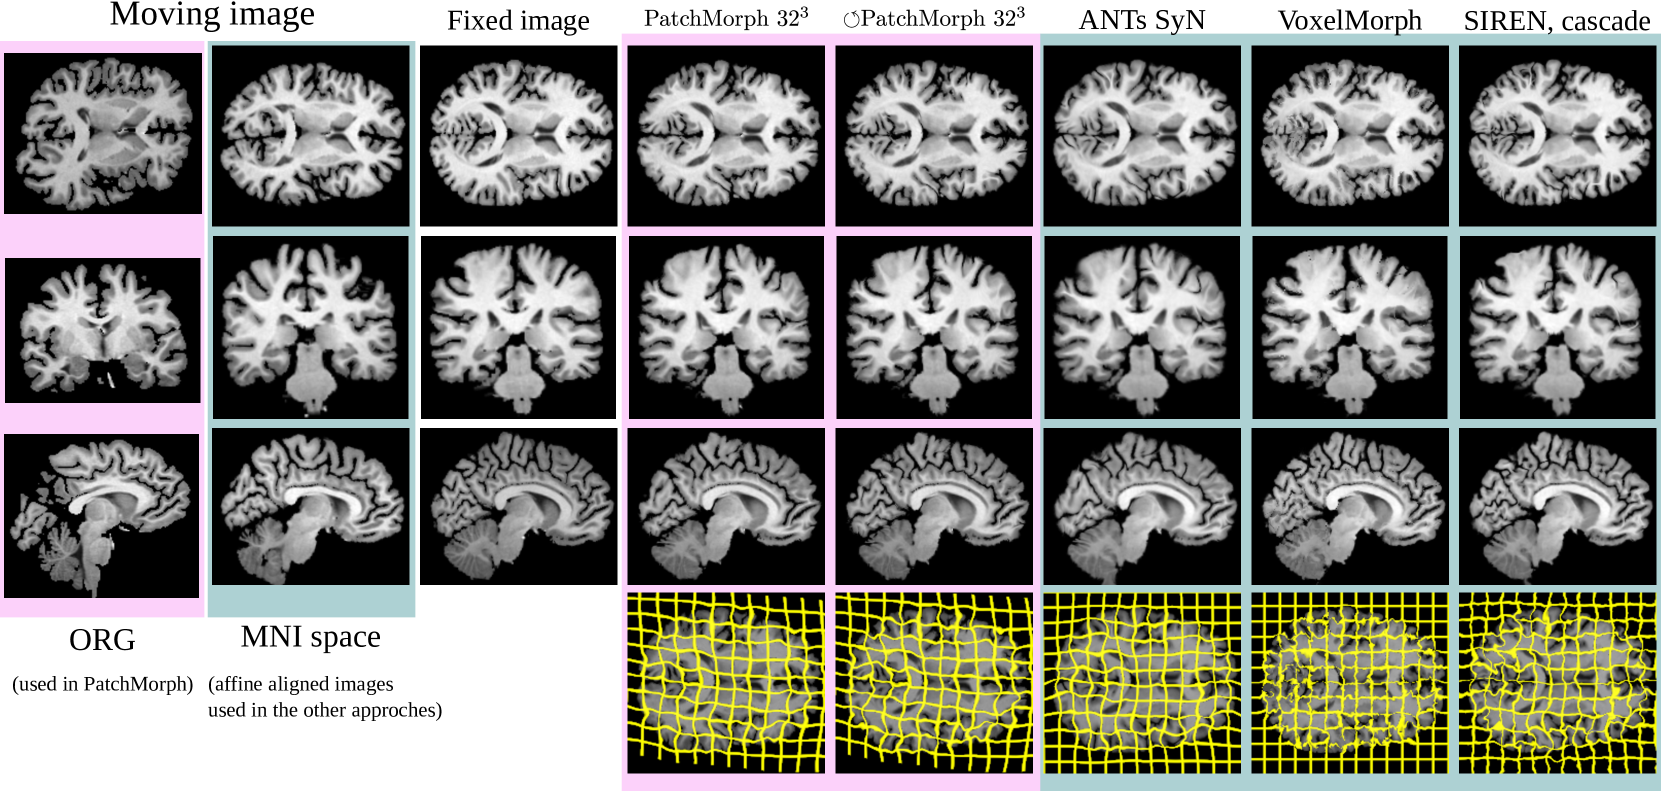

Refer to caption

Figure 9: A qualitative example from the MindBoggle experiment. For PatchMorph, we used the original image as moving image, while for the other approaches, we used the affine pre-alinged version. PatchMorph and ANTs exhibit the smoothest warp fields, while maintaining good registration results.

We benchmarked PatchMorph against the methods evaluated in our prior study on implicit neural representation networks (INRs) [13]. As some methods necessitate pre-aligned images, comparative analyses were performed on affine-aligned brain images. Our comparison included a standard Affine baseline, ANTs SyN registration, diffeomorphic VoxelMorph (D-VMorph), and SIREN, the highest-performing INR model from  [13].

The results for PatchMorph are shown in the upper section of Table 2, and the comparative analyses are shown in the lower section. Figure 9 shows qualitative results for one example.